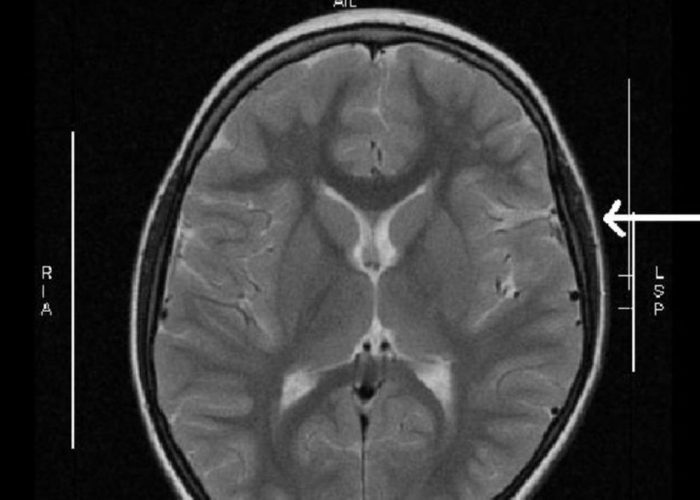

The study, published Wednesday in Neurology, looked at data from more than 3 million patients enrolled in a single private health care plan. They looked at health care services related to neurology, such as evaluation or management visits with doctors, electromyograms (used to test the connection between our muscles and nerve cells), as well as MRIs and other brain imaging exams. The study period spanned from 2001 to 2016.

Patients are also paying more upfront for these exams and tests over time, though the actual costs fluctuate wildly. The median cost of a MRI test on its own in 2016 was $103, for instance, but costs can go high as $875 for those above the 95th percentile of patients in the new study. People enrolled in high deductible health plans are also often paying even more than others.